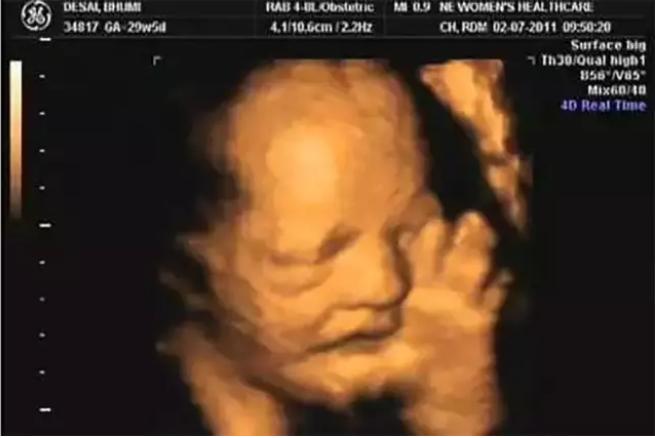

孩子为什么会吃手呢?一是婴儿吃手属于原始反射,当婴儿还在妈妈肚子里八个月时就会伴随吸吮反射出现,这种行为可助孩子出生后顺利吸到母乳。因此有的父母从做 B 超就能看到孩子在吃手,但这仅是一种本能行为。